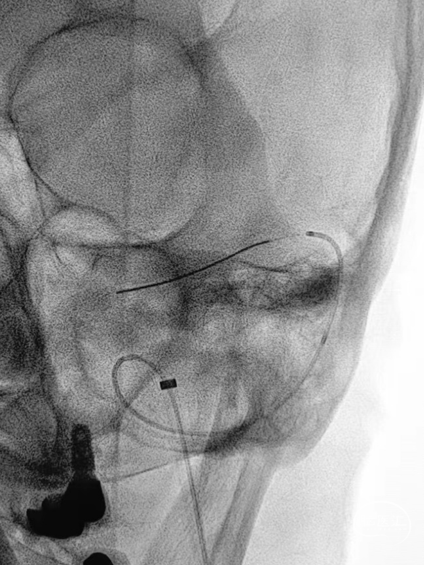

➤DSA

6F 长鞘导引至左侧颈内静脉末端。

测压导丝对横窦至乙状窦进行测压,静脉压差<2mmHg,未对狭窄段进行球囊扩张。

6F 长鞘导引至左侧乙状窦。

交换Command 18导丝超选至左侧横窦,将Echelon-10微导管置入静脉窦憩室。

路图下,沿Command 18导丝将8×40mm Xpert Pro支架输送至乙状窦,使用支架近远端marker点进行准确定位,整个推送过程顺利,无明显阻力。

Xpert Pro支架未展开状态下在憩室内尝试使用弹簧圈进行填塞,发现成篮困难。

随即释放Xpert Pro支架以覆盖憩室开口,支架打开后显影清晰,贴壁良好。使用微导管穿出支架网孔,并置入憩室内进行弹簧圈填塞。单微导管填塞过程弹簧圈成篮较为困难。

使用双导管继续在Xpert Pro支架辅助下进行弹簧圈填塞,再次造影显示:憩室内血液已完全阻滞,未见显影。

Xpert Pro支架在乙状窦内形态良好。静脉窦憩室闭塞完全。